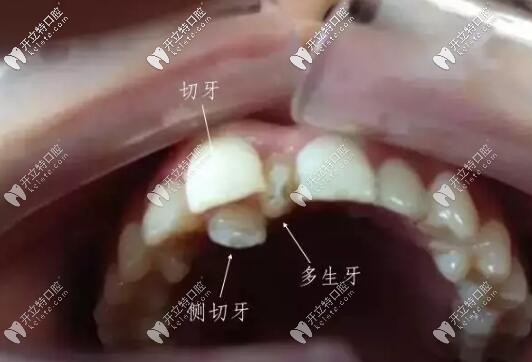

萌出的多生牙

智齒和多生牙并不是一個概念。多生牙從形態(tài)、牙根的數(shù)量,均不同于正常牙。

多生牙:多生牙是額外牙齒,是除20顆乳牙和32顆恒牙以外的牙齒。

多生牙一般分萌出和不萌出埋伏阻生兩種,有些牙齒還倒長。

多生牙在任何牙位都可能發(fā)生多生牙,但常見的是上頜“正中多生牙”,其后,依次排為上頜第四磨牙等。